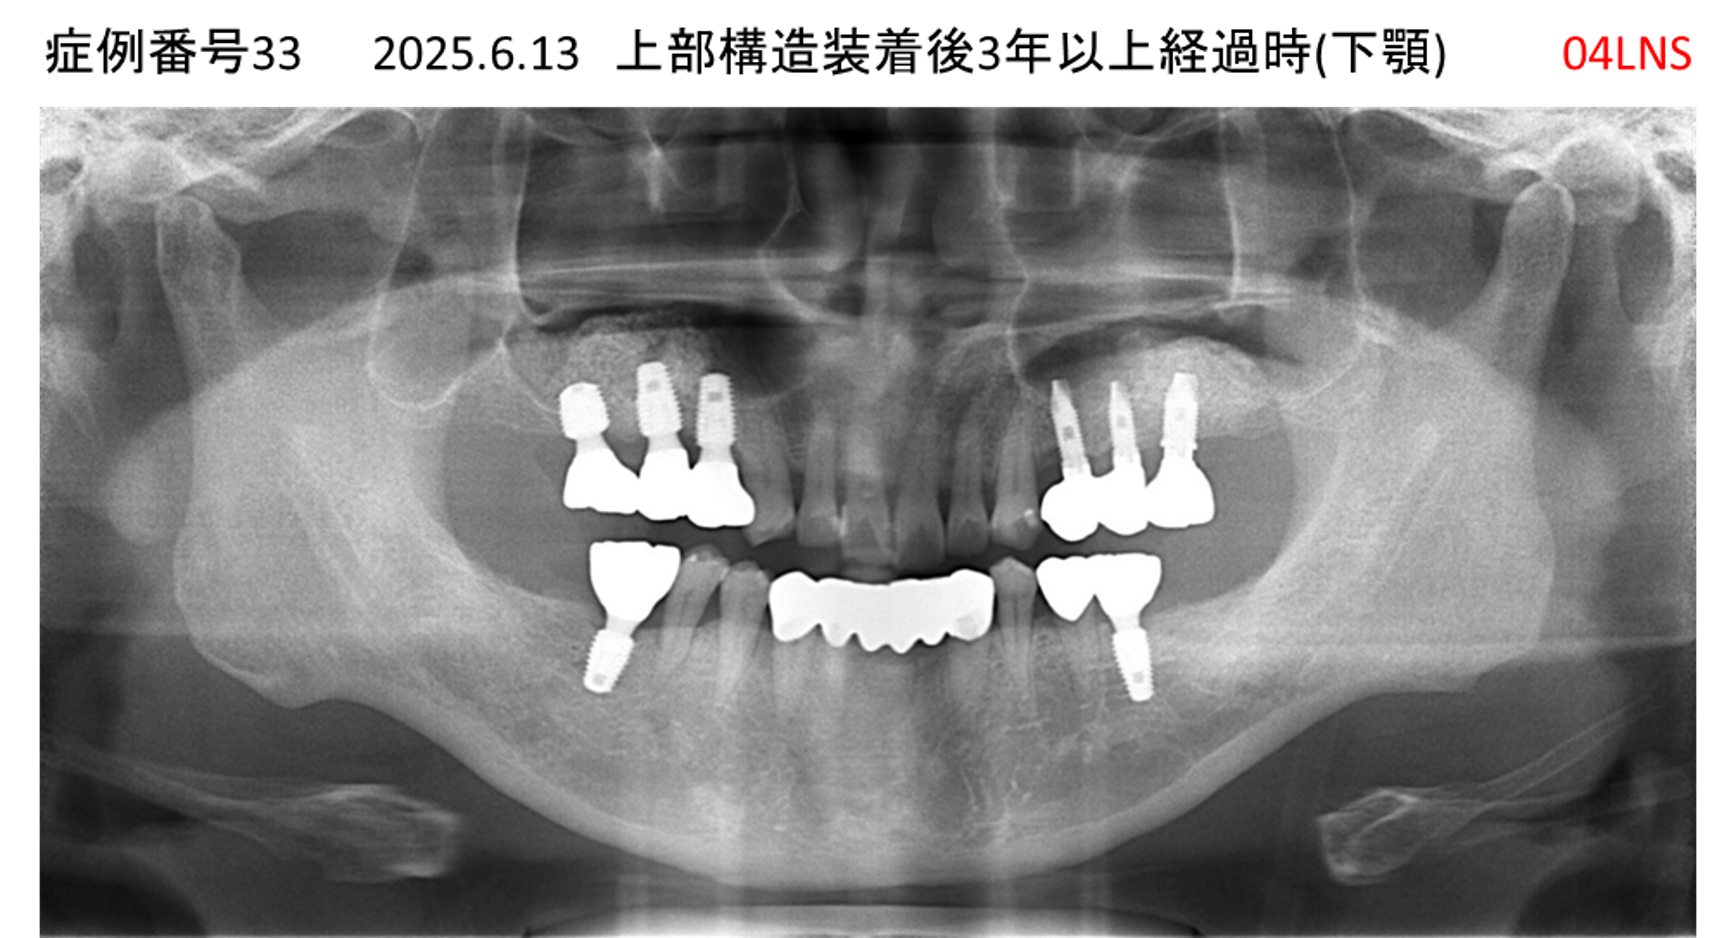

ご飯を美味しく食べたい/人前で笑えるようになりたい患者様のインプラント症例

| 治療名称 |

インプラント |

| 治療費用 |

480万円+税 |

| 治療期間 |

6か月 |

| 患者さんの症状(主訴) |

おいしいご飯が食べられるようになりたい 人前で笑えるようになりたい |

| 治療内容 |

サイナスリフト 抜歯即時インプラント |

| 治療結果 |

何でも食べられるようになった 人前で大口を開けて笑えるようになった |

| 治療の注意点(リスク/副作用) |

インプラントが壊れた場合は再治療が必要 |